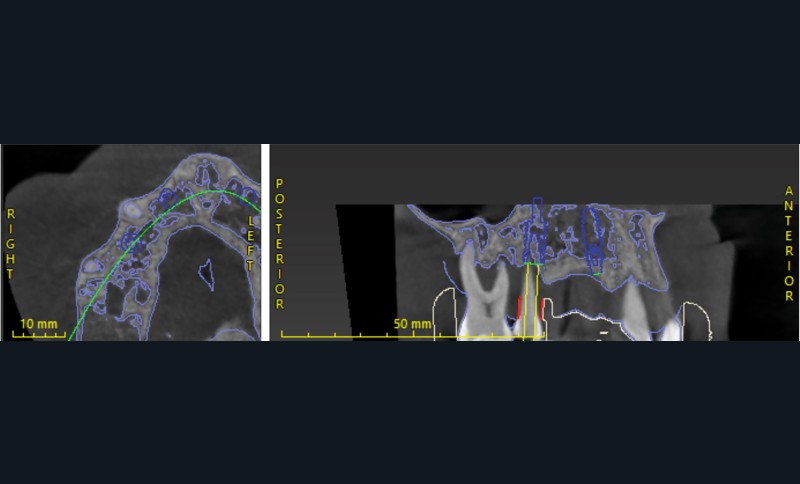

L’empreinte optique, les photographies et le CBCT ont permis une fusion précise des données numériques pour planifier les axes et positions implantaires en fonction du projet prothétique final (fig. 3, 4).

Cette planification a ainsi intégré la future ligne d’émergence et la gestion anticipée des tissus mous [2].